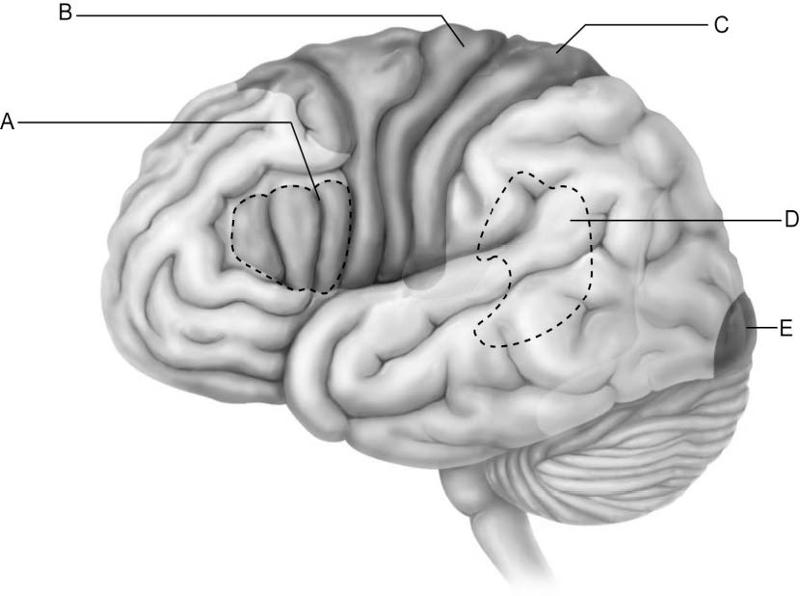

Which letter indicates the primary visual cortex, which receives

information from neurons in

the retina of the eye?

A)

A

B) B

C) C

D) D

E) E

E

Which letter indicates Broca's area, which controls the motor

movements necessary for

speaking?

A) A

B) B

C)

C

D) D

E) E

A

Which letter indicates Wernicke's area, which is important for

understanding spoken words?

A) A

B) B

C) C

D)

D

E) E

D

Which letter indicates an area that is characterized by huge neurons

known as pyramidal cells?

A) A

B) B

C) C

D)

D

E) E

B

Which letter indicates the primary somatosensory cortex?

A)

A

B) B

C) C

D) D

E) E

C